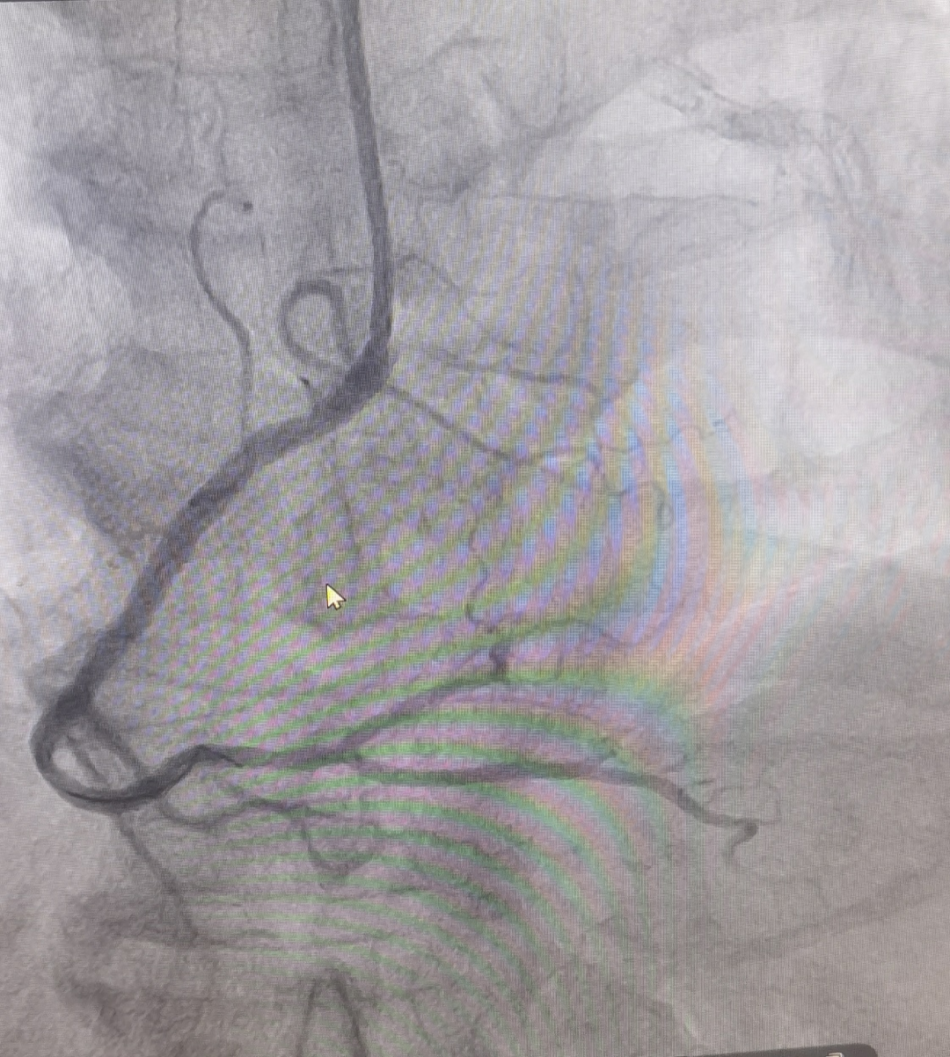

(圖為生物可吸收支架置入術后影像)

冠脈支架置入術歷史悠久,對冠脈重度狹窄患者效果確切。但是傳統支架一般都是金屬支架,置入后需長期服藥,并且支架一直保留在體內。隨著醫療技術的發展,生物可吸收支架是一項令人鼓舞的新技術,已初步表現出良好的治療效果和樂觀的應用前景,其獨具的可被完全降解吸收的特點,使支架本身能逐漸被人體組織吸收、降解、恢復靶血管的生物性,達到冠脈介入治療真正的“微創、無痕”的預期效果。另外,生物可吸收支架的置入避免金屬植入物永久存留體內的問題,對于年輕患者來說遠期效益更大。值得注意的是,為了達到更好的治療效果,術者應嚴格把握適應癥的選擇,同時在手術過程中要嚴格遵守PSP(充分預處理-選擇合適的支架尺寸-充分的后擴張)操作規程。